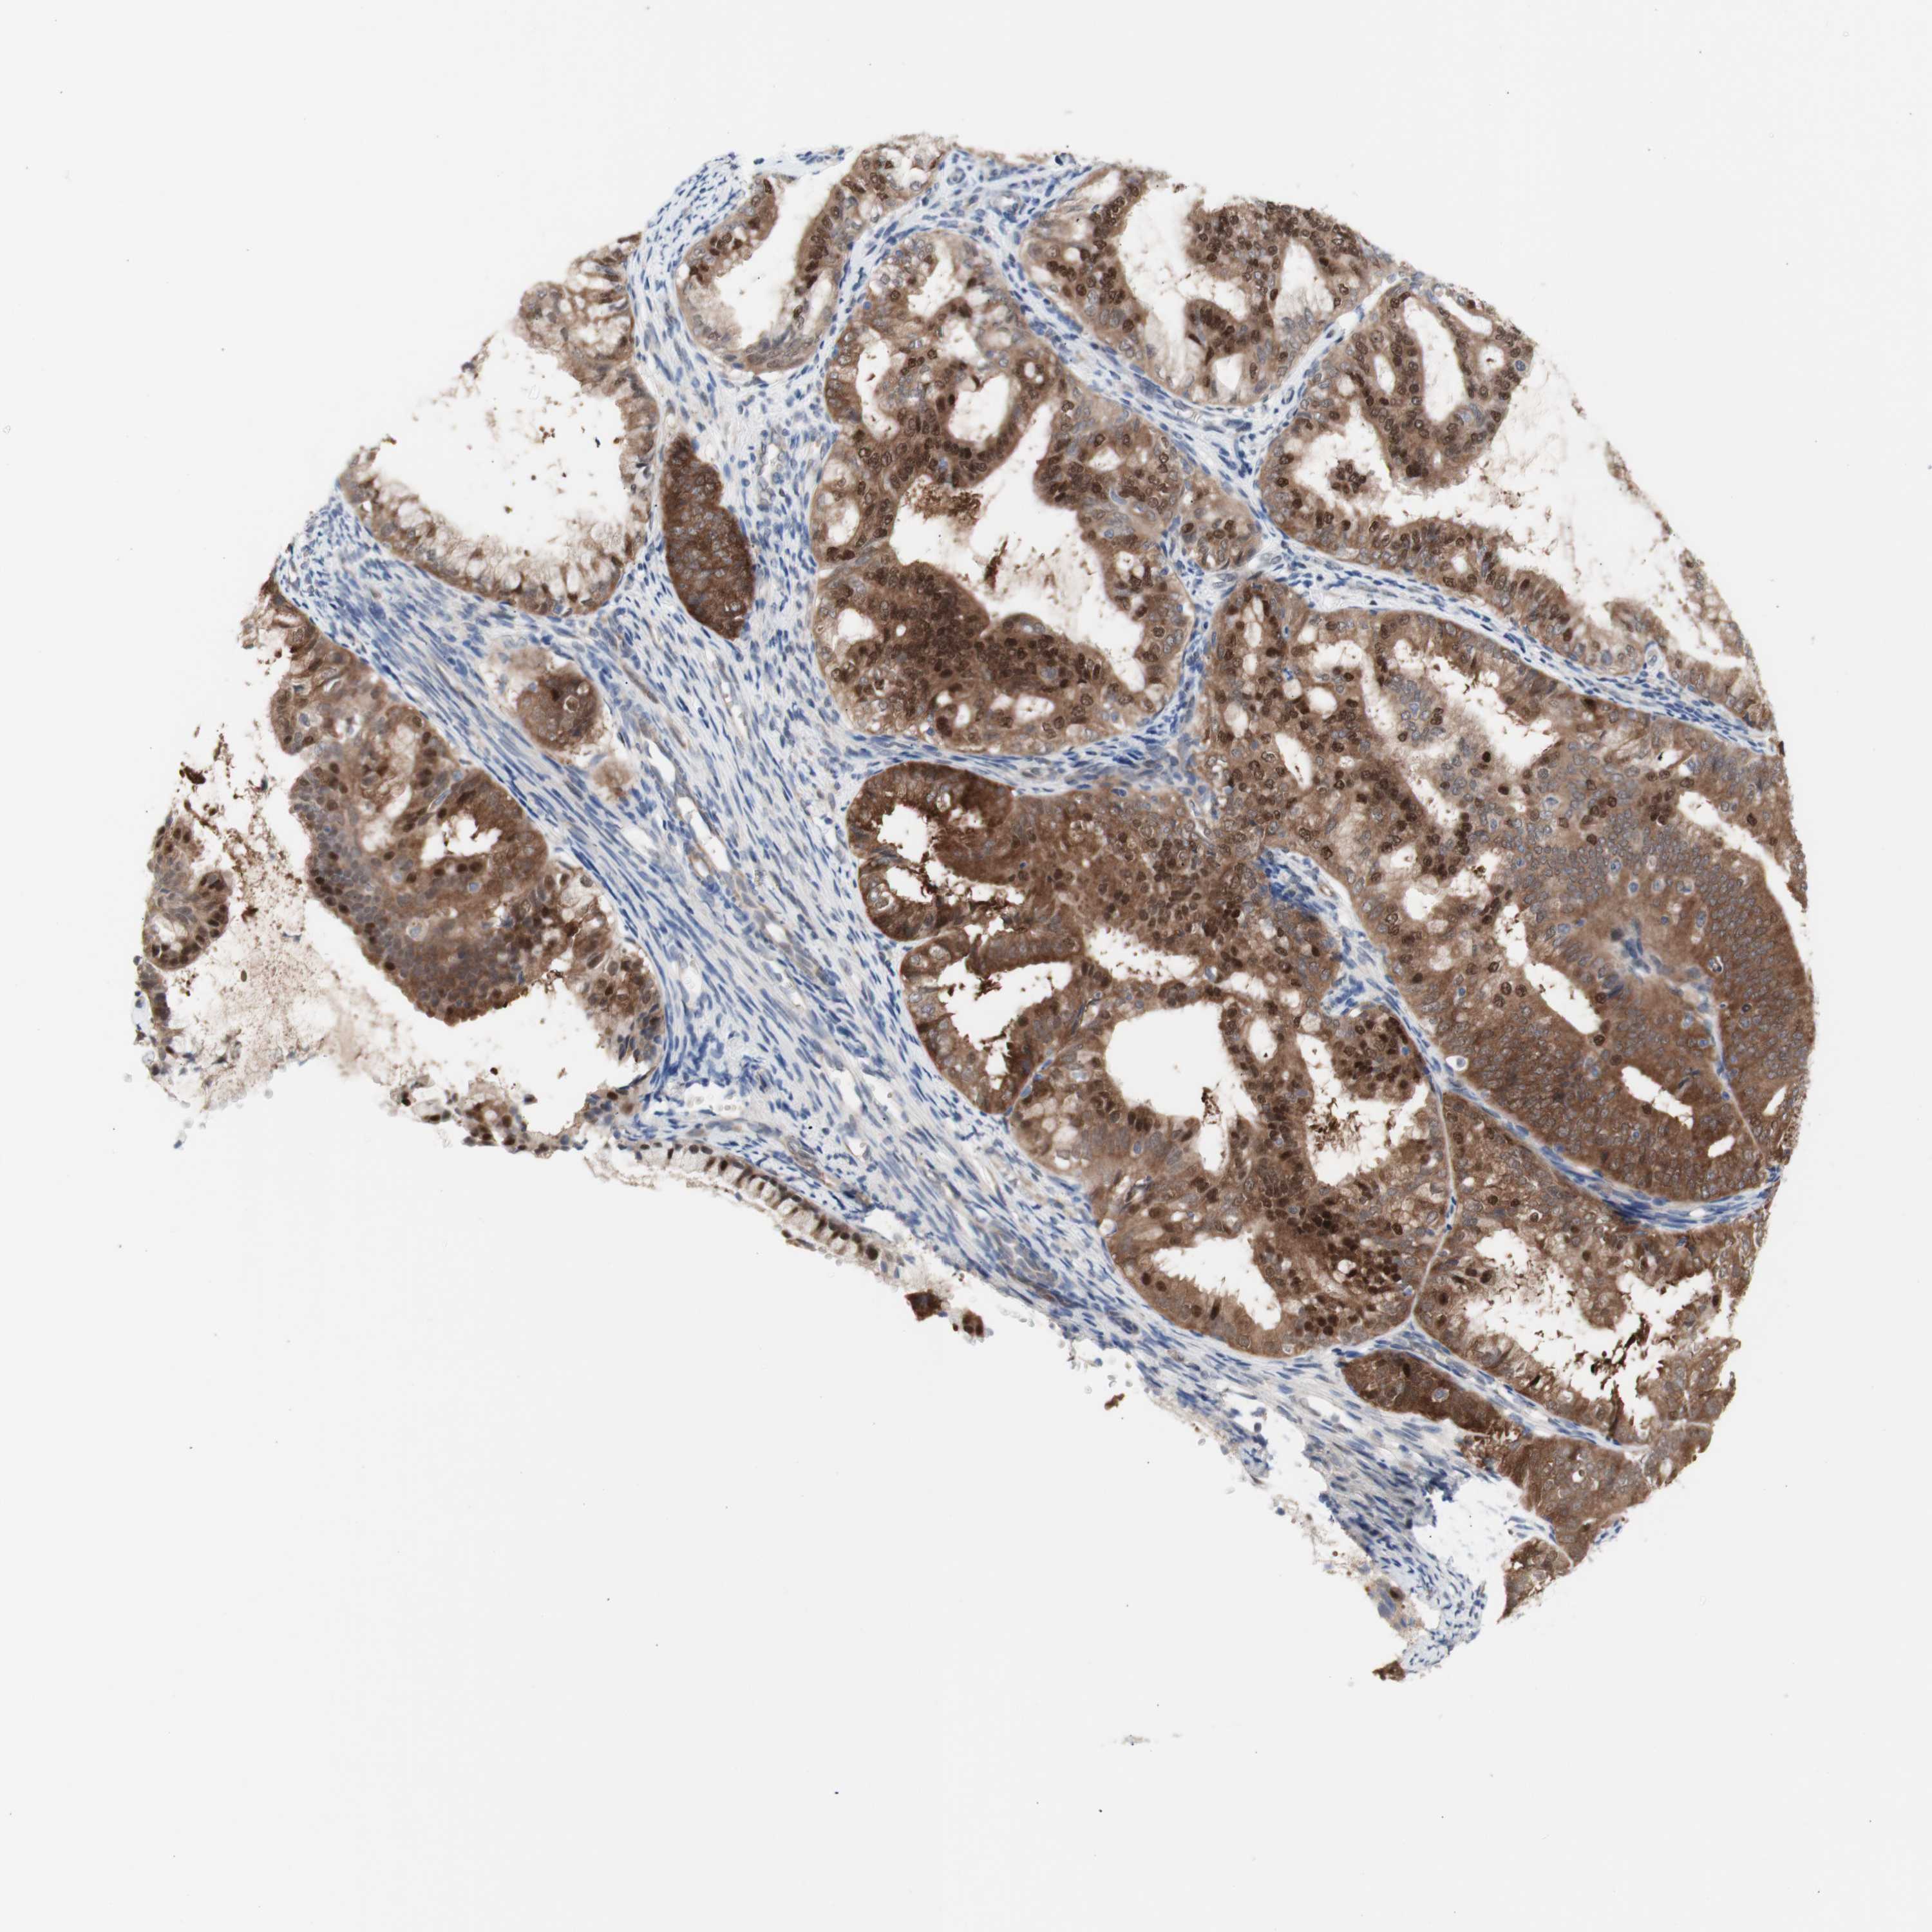

ENDOMETRIAL CANCER - Protein expressioni

A mouse-over function shows sample information and annotation data. Click on an image to view it in a full screen mode. Samples can be filtered based on level of antibody staining by selecting one or several of the following categories: high, medium, low and not detected. The assay and annotation is described here.

Note that samples used for immunohistochemistry by the Human Protein Atlas do not correspond to samples in the TCGA dataset.

Antibody stainingi

Antibody staining in the annotated cell types in the current human tissue is reported as not detected, low, medium, or high, based on conventional immunohistochemistry profiling in selected tissues. This score is based on the combination of the staining intensity and fraction of stained cells.

Each image is clickable and will lead to virtual microscopy that enables deeper exploration of all samples and also displays staining intensity scores, fraction scores and subcellular localization as well as patient and tissue information for each sample.

Antibody HPA005525

Antibody HPA064708

Antibody CAB012459

Staining

High

Medium

Low

Not detected

Intensity

Strong

Moderate

Weak

Negative

Quantity

>75%

75%-25%

<25%

None

Location

Nuclear

Cytoplasmic/membranous

Cytoplasmic/membranous,nuclear